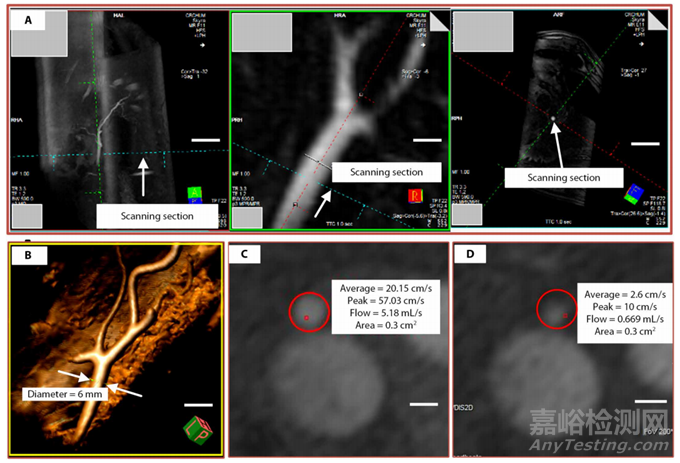

圖5 控制和測量血流的程序

高流速會降低MRN的效率,因為在較短時間內(nèi),微弱的磁轉(zhuǎn)向力沒有足夠的時間向目標(biāo)葉瓣偏轉(zhuǎn)。另一方面,低流量會導(dǎo)致微型機(jī)器人由于重力和摩擦而粘附在血管底部。肝主動脈的血流速率應(yīng)在0.5~1.0 ml/s之間,以優(yōu)化MRN。圖5說明了測量血流速率的程序。從肝固有動脈橫切面的影像相位對比圖像中測量血流率,氣球充氣后控制流量為0.7 ± 0.3 ml/s。